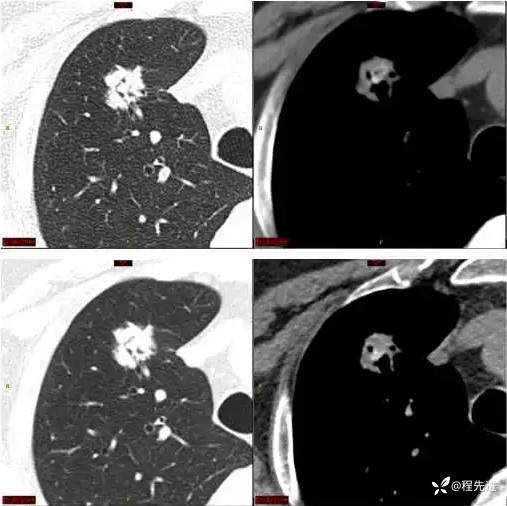

CT平扫:

上排与上面同时间,下排是3月后复查